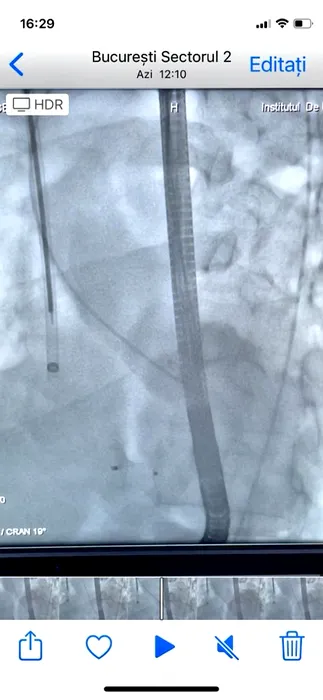

EXCLUSIV. Pacient cu infarct devastator salvat printr-o intervenție de excepție, la Institutul Inimii din Capitală, de echipa medicului Dan Deleanu. Ce presupune intervenția (FOTO)